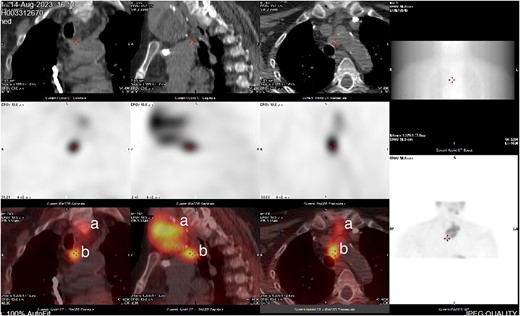

She was subsequently referred to our service for further surgical evaluation. At the time of referral, she was asymptomatic. Initial blood tests showed an elevated PTH of 1256 pg/ml (range 15–65 pg/ml), reduced adjusted calcium of 2.05 mmol/l (range 2.21–2.52 mmol/l), normal free T4 at 19.9 μg/dl (range 12–22 μg/dl), and a reduced TSH <0.01 mU/l (range 0.27–4.20 mU/l), along with a raised phosphate of 2.32 mmol/l (range 0.81–1.45 mmol/l). A CT neck showed a large left thyroid mass with a differential diagnosis of metastatic lymphadenopathy versus a parathyroid adenoma. She underwent an ultrasound and fine needle aspiration of the thyroid mass, which revealed a Thy3A lesion with no evidence of malignancy. Following further multidisciplinary team (MDT) discussion, an immunostain for PTH was performed on the EBUS TBNA, which revealed that the oncocytic cells were positive for PTH (see Figs 1 and 2). This was confirmed by a sestamibi scan, which confirmed a sestamibi-avid nodule (see Fig. 3).

CT neck and sestamibi scan of coronal, sagittal, and axial view of superior mediastinum with mediastinal ectopic parathyroid nodule. (a) Thy3A thyroid nodule; (b) mediastinal parathyroid nodule.